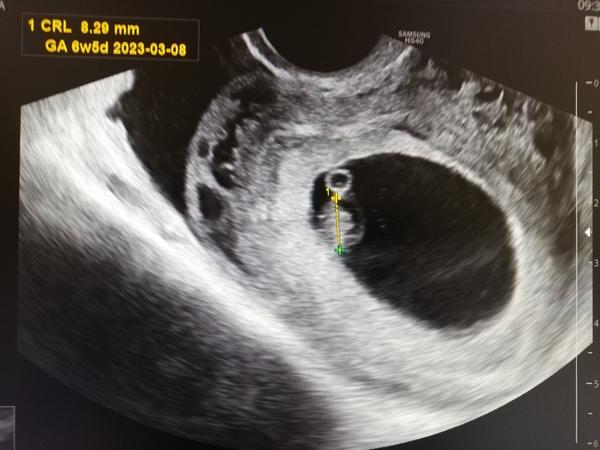

@renat23 termín mi dal 8.3. Ale u každého těhu mi dal termín o týden pozdější a pak se to srovnalo, takže těch 4.3 bude odpovídat. Dneska podle něj 6+5 a má 8mm. Na kontrolu jdu až 23.8, těsně před screeningem. Zdá se mi to jako šíleně vzdálená doba. Ale zítra si ještě skočím nakrev kvůli štítné žláze.